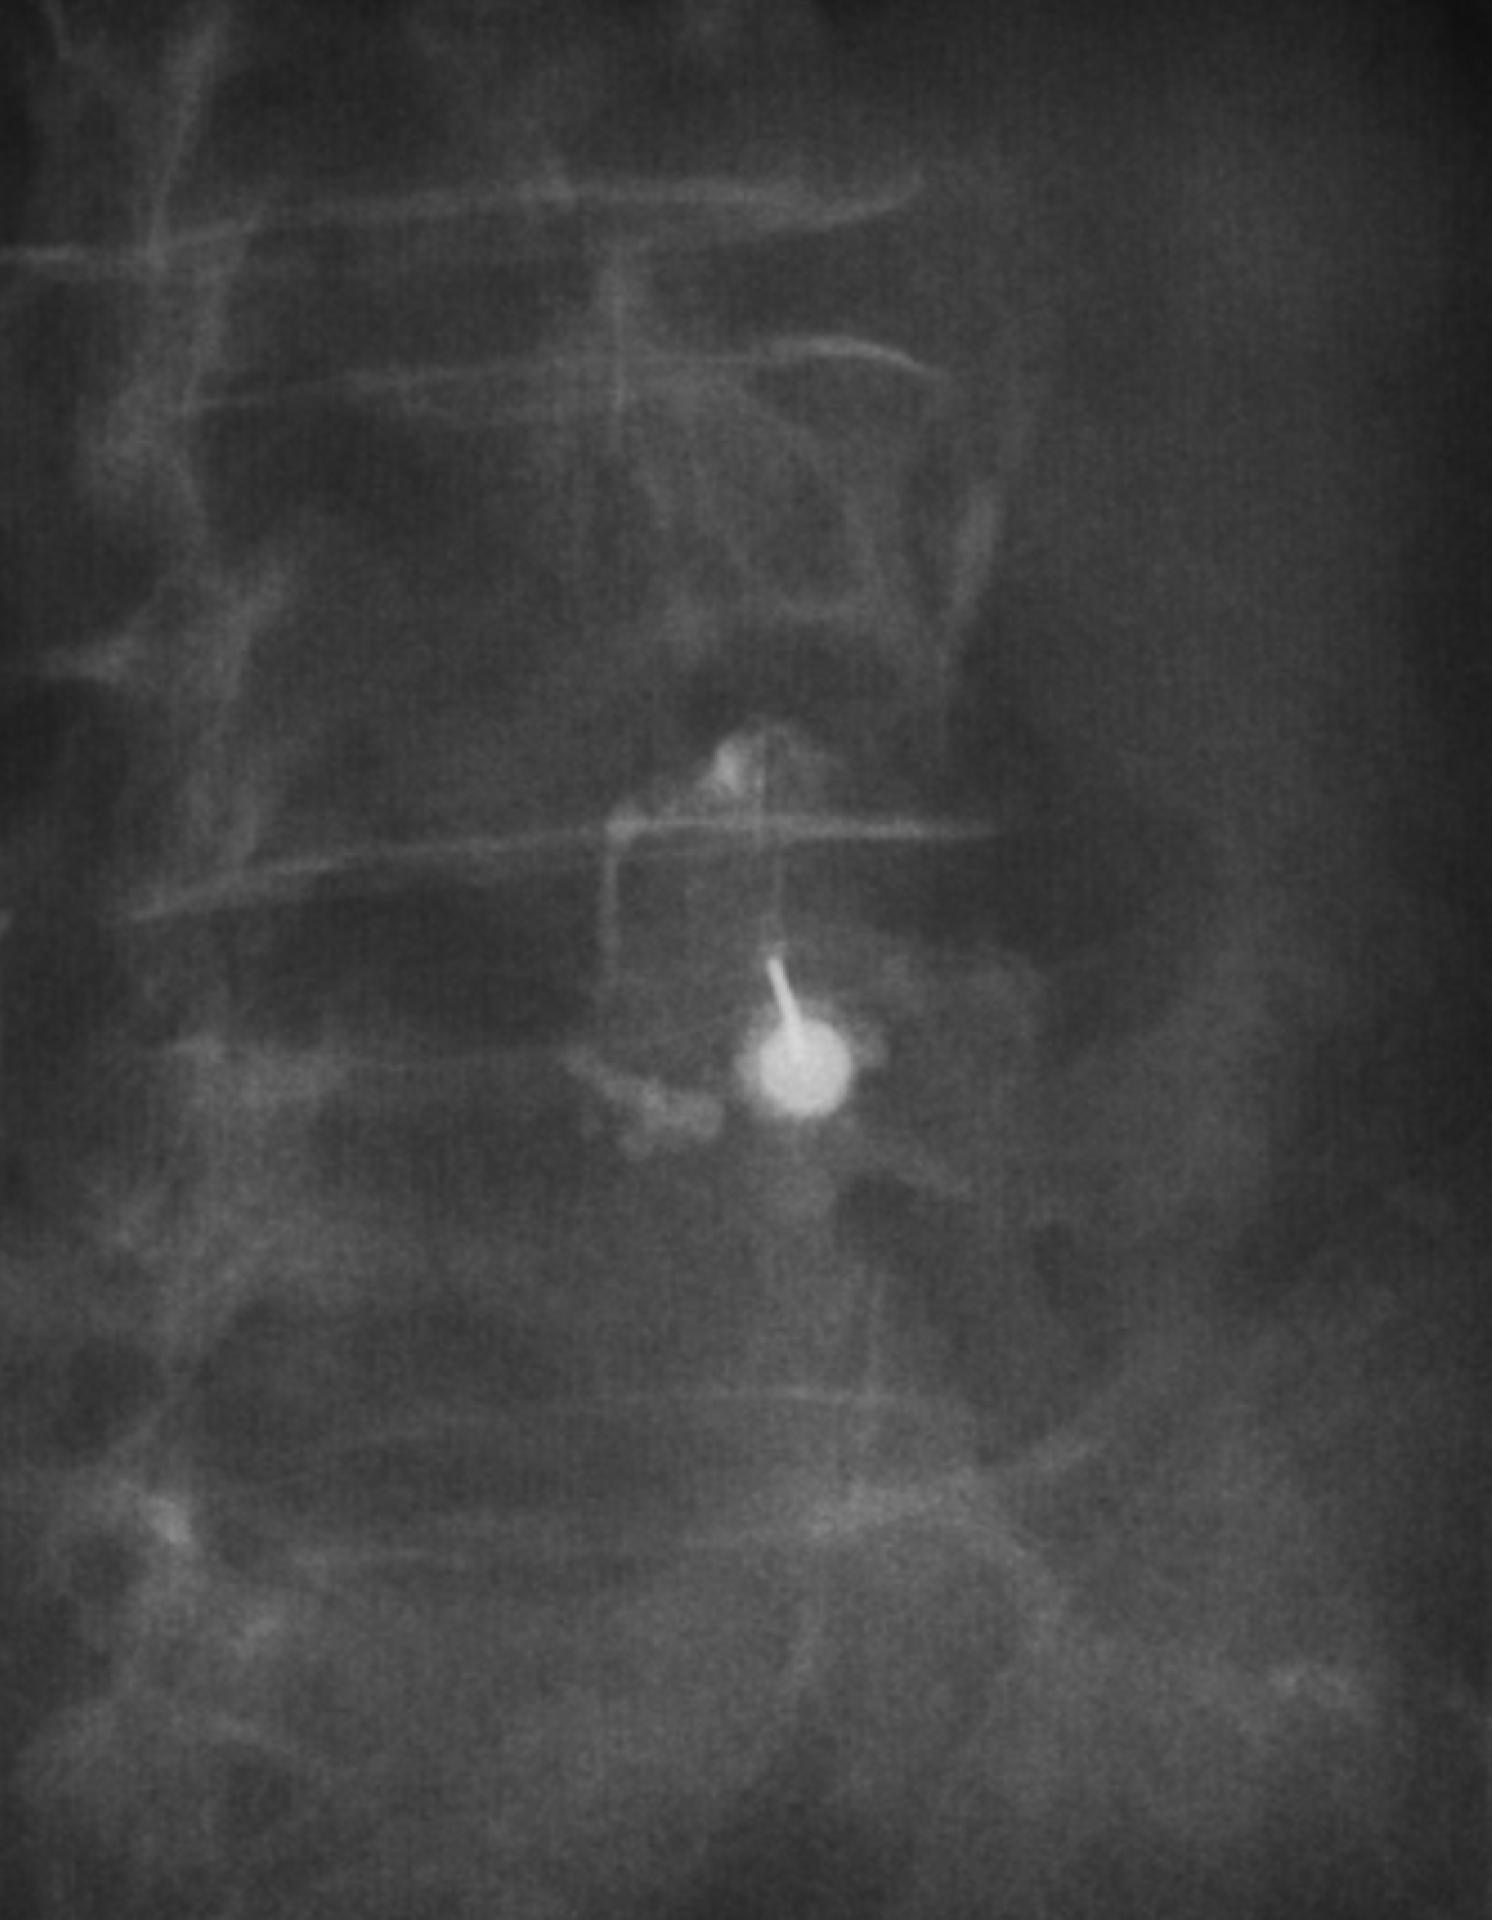

Infiltration sacro-iliaque scannerisée pour sciatalgie à prédominance mécanique à Aubagne

L’infiltration sacro-iliaque scannerisée est une solution précise et efficace pour traiter la sciatalgie à prédominance mécanique chez les patients d’Aubagne. Grâce à l’imagerie médicalisée, cette technique permet un soulagement ciblé de la douleur lombaire ainsi qu’une amélioration notable de la ...

Infiltration articulaire postérieure sous contrôle scopique à Marseille

Nos centre d'imagerie médicale Marseille Lodi, La Rose et Fuveau réalent les infiltrations articulaire postérieure sous contrôle radiographique. Après avoir nettoyé la peau, nous positionnons une aiguille au niveau d'une des articulations postérieures de la colonne vertébrale. Une anesthésie est r...